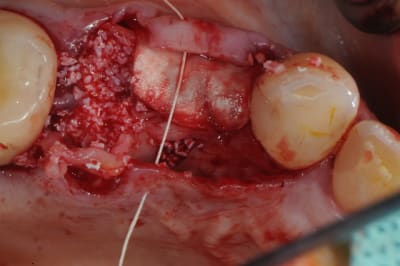

pour débuter ce post je propose un petit cas avec une ROG un comblement alvéolaire et un lambeau pédiculé pour fermer le site d'extraction.

au début incision supra crestal puis lambeau muco-périosté.

avec une simple lame 11 qui tranche le long de gencive palatine. évidemment c'est le plus dure à faire pour éviter de transpercer ou d'avoir d'un coté ou de l'autre une épaisseur trop faible.

Au maxillaire je procède de la même manière: extraction, curetage, comblement et greffon conjonctif pédiculé. Le punch épithélio-conjonctif ne m'a pas vraiment donné jusqu'à présent de meilleurs résultats que le conjonctif pédiculé et en post-op je trouve que c'est plus douloureux pour le patient.

un petit exemple de ce matin: extraction des piliers 12 et 14, curetage, comblement avec du bio-oss de la dépression osseuse vestibulaire au niveau de l'inter 13, comblement des alvéoles 12 et 14 au genos et recouvrement par 2 pédicules conjonctifs. Temporisation avec un partiel amovible.